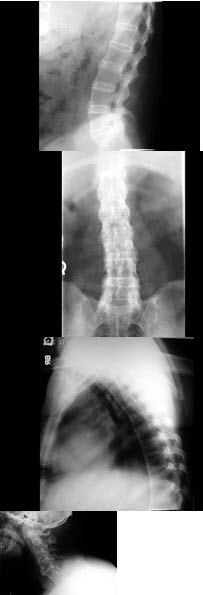

19、单项选择题

男,65岁,腰背部疼痛1月余,结合图像,最可能的诊断是()

A.脊椎结核

B.椎体压缩骨折

C.脊椎退行性变

D.脊椎转移瘤

E.L2~L3椎间盘炎

286、单项选择题

男,21岁,腰部不适,晨起加重半年余,X线检查如图,最可能的诊断是()

A.类风湿关节炎

B.脊椎退行性变

C.强直性脊柱炎

D.化脓性脊柱炎

E.阻滞椎